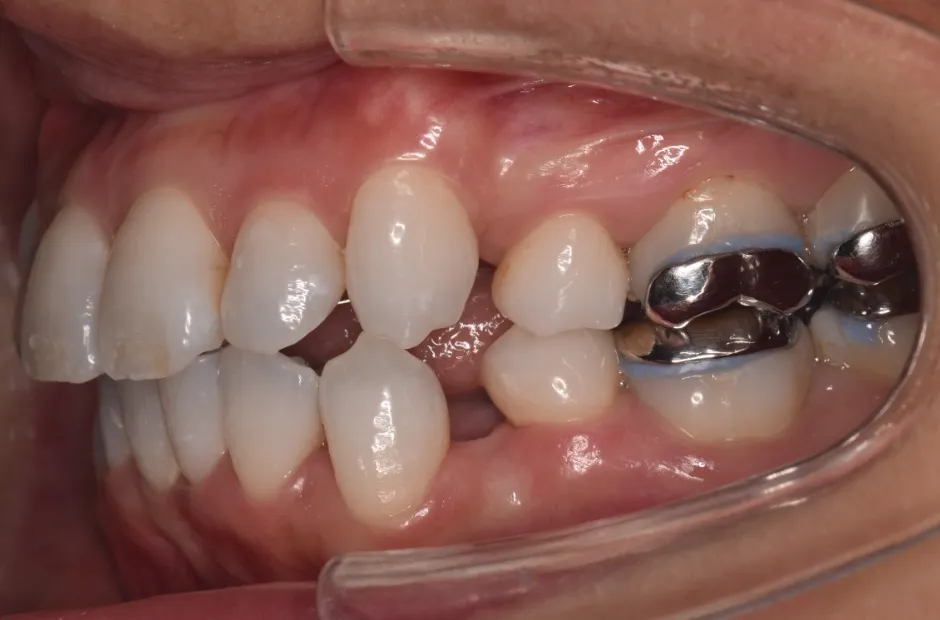

叢生

| 診断名・主訴 | 叢生 |

|---|---|

| 年齢・性別 | 43歳・女性 |

| 治療期間・回数 | 2年7か月 27回 |

| 治療に用いた主な装置 | 舌側矯正 |

| 抜歯部位 | 両顎4,4 |

| 治療費 | 100万円(税抜) |

| リスク・副作用 | 装置による違和感・疼痛・歯肉退縮・歯根吸収・虫歯のリスクなど |

治療前

治療中

治療後